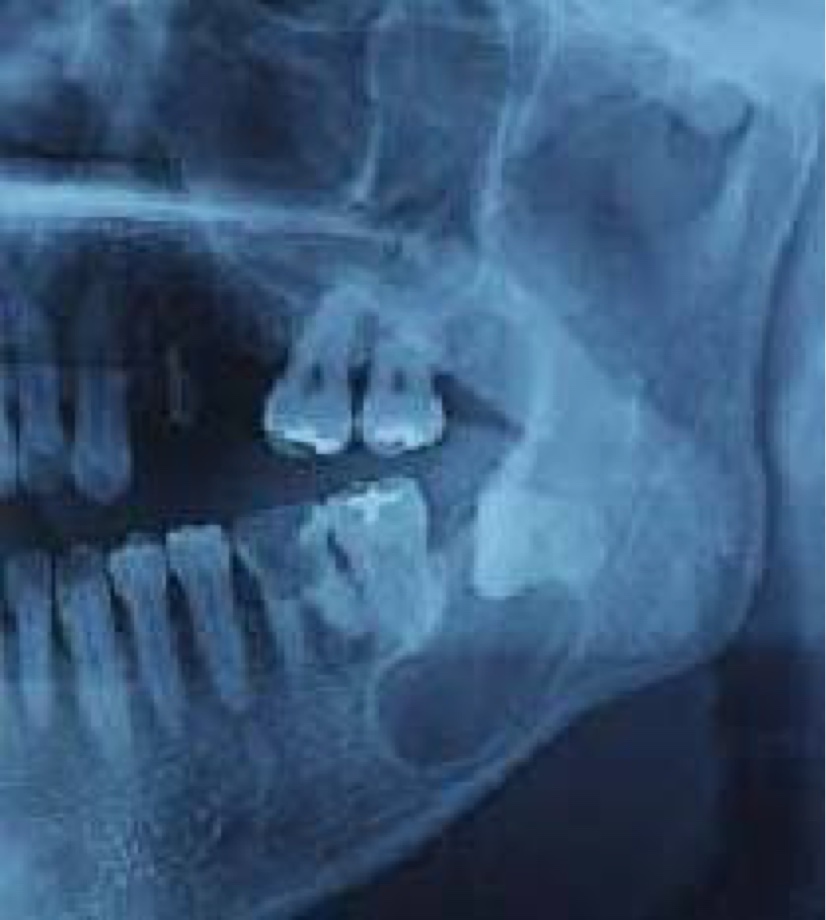

病名は【顎骨(がっこつ)嚢胞(のうほう)】

写真は以下(ネットから拝借)

下顎の埋没している親知らずの所に風船状に見える物が嚢胞というそうで風船の中は半流動体でどんどん大きくなってきます。

厄介な事に大きくなる為に顎(あご)の骨を溶かしてしまい、放置すると顎の骨に穴を空けてしまうそうで、そうなると歯がぐらついたり、腫れたりします。

写真の通り風船の下部の骨はかなり薄くなっていてこれを放置すると穴が空きます。

私の場合はまさに穴が空く一歩手前で写真と同じ感じでした。